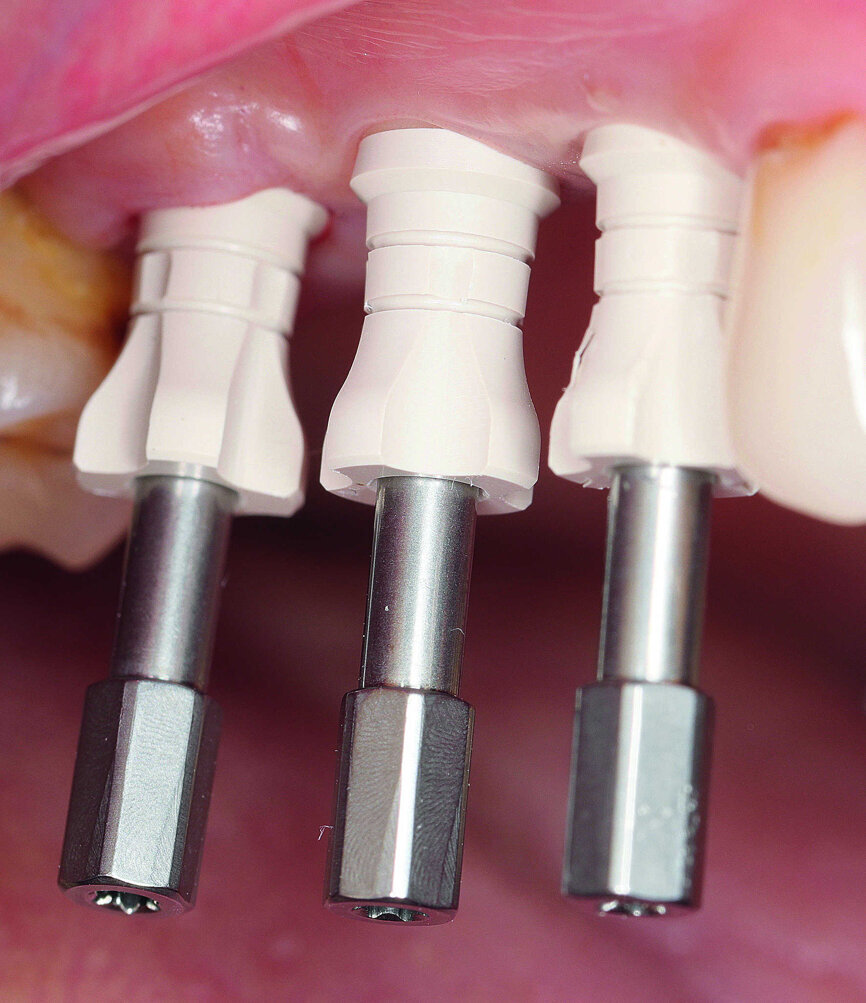

Fig. 22 : Essayage des piliers.

Six jours après la commande, le laboratoire a reçu les piliers produits par CAD/ CAM. Le modèle de la connexion interne était adapté à la zircone et garantissait une distribution optimale des forces. En raison des limitations de l’usinage des rayons, les piliers en zircone (DEDICAM, CAMLOG) ont été fabriqués selon le concept dit du « platform-switching », où le diamètre du pilier est inférieur à celui du col de l’implant. Les piliers ont été vissés au laboratoire et le potentiel hygiénique des parties sous-gingivales a été vérifié (Fig. 21). Une autre étape importante était la restauration par des couronnes prothétiques robustes. À cette fin, des prototypes en polyméthacrylate de méthyle ont été préparés par impression 3D, sur la base des données STL existantes. Avec ces couronnes synthétiques économiques, l’occlusion, les points de contact, le potentiel hygiénique ainsi que la forme et l’esthétique peuvent être vérifiés en bouche durant l’essayage des prototypes. Le platform-switching intégré et la hauteur de la structure occlusale n’ont pas permis l’obtention d’une esthétique idéale du profil d’émergence coronaire de la région dentaire 16 (Figs. 22 et 23). Cet inconvénient a cependant été jugé cliniquement acceptable, en raison de l’accumulation moindre de la plaque sur la zircone et de la facilité de nettoyage de cette surface dans la structure hybride pilier-couronne résultante.9,10 Grâce à la solide planification prothétique en amont, les couronnes en zircone – dont la face vestibulaire est stratifiée ultérieurement – ont pu être fabriquées avec un puits d’accès à la vis sur la face occlusale. Après leur finition, les couronnes ont été collées sur les piliers, pour obtenir des structures hybrides pilier-couronne monobloc de forme entièrement anatomique. La fonction et l’esthétique ont été vérifiées et les structures hybrides pilier-couronne ont été fixées en bouche par des vis en titane, avec un couple de serrage de 25 Ncm.